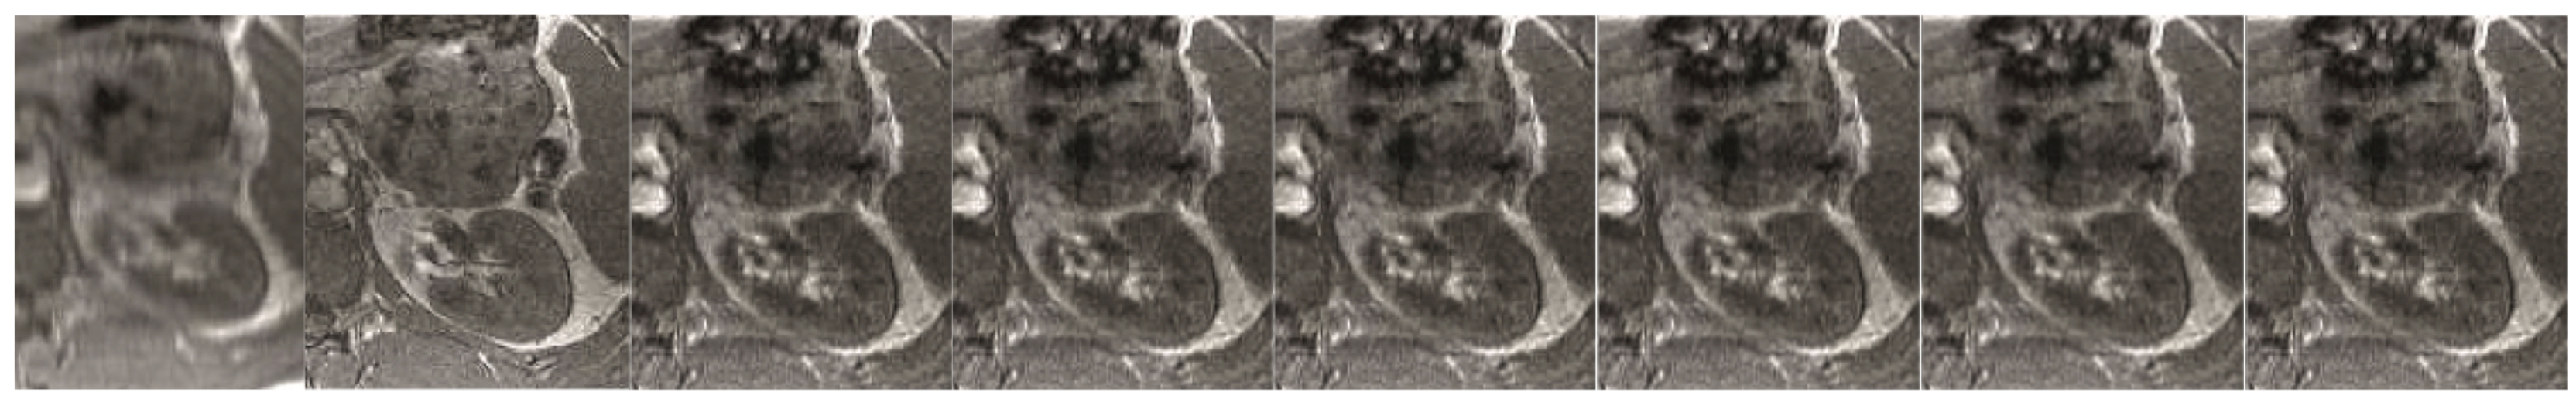

Figure 8. The abdominal image processing. From left to right: A: Image reconstructed from partially sampled PROPELLER blade, B:Cartesian sampling grid without image registration applied (with no downsampling applied), C: B-spline Cubic interpolation, D: Non-Rigid Multi-Modal 3D Medical Image Registration Based on Foveated Modality Independent Neighbourhood Descriptor [45], E: Enhanced deep residual networks for single image super-resolution [14], F: Image super-resolution using very deep residual channel attention networks [16], G: Residual dense network for image super-resolution [15], H: super-resolution with proposed sampling scheme and motion compensation (the proposed algorithm). Compression ratio is 50%. Please see Table 3 for the PSNR values at other compression ratios.